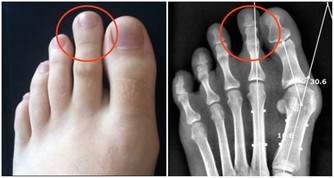

1、不選人字拖

人字拖不能給腳部足夠的支撐面,老人走路時會不自覺地用腳趾摳住鞋底。腳趾長時間處於屈曲狀態,會出現酸麻、僵硬、跟腱疼痛等症狀。

因此,老人選鞋面是一整塊的拖鞋更為舒適、安全。